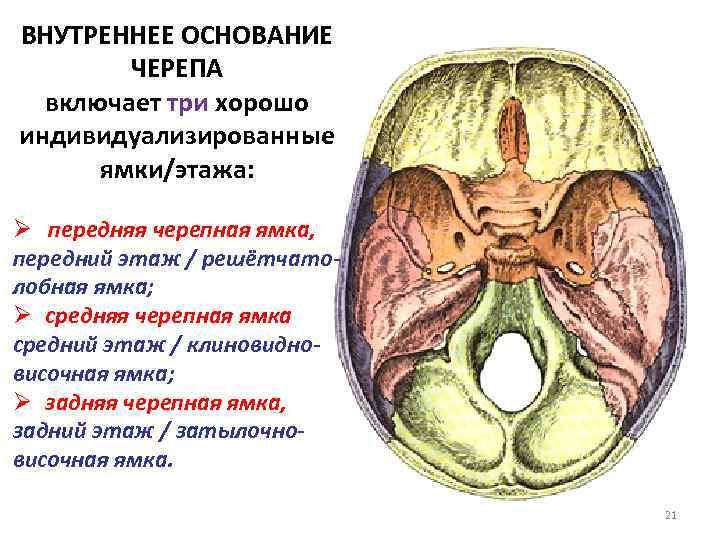

Анатомические детали: Фотографии топографии черепа с нижнего вида